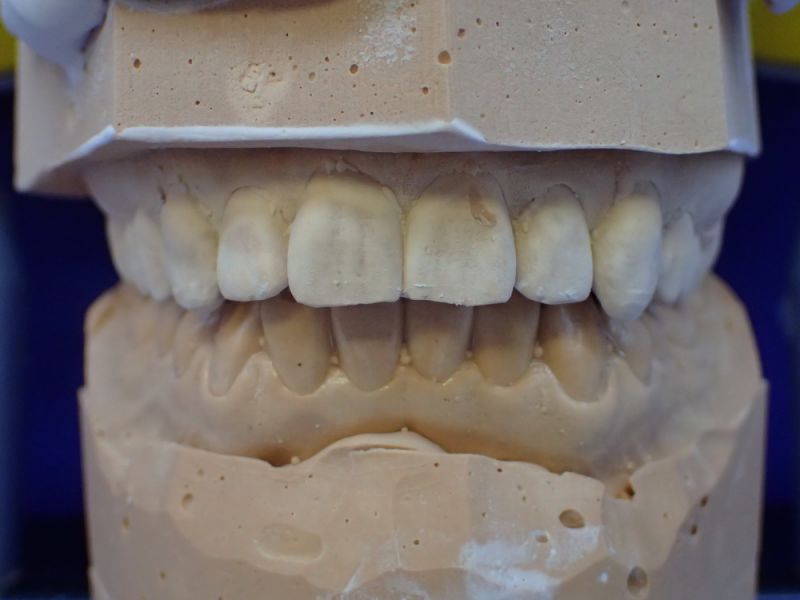

Es erfolgen die Maßnahmen der funktionellen Erstuntersuchung und die Herstellung und Eingliederung eines adjustierten Aufbissbehelfs zum Nachweis einer CMD.

Mann kann hier sehr gut an den beiden Punkten der distalen Dreipunktabstützung erkennen, mit welch hoher Passgenauigkeit die Zentrikplatten auf die Gipszähne der Meistermodelle aufgebacht werden können und müssen.

Es ist einer dieser Detailpunkte, der darüber entscheidet, mit welcher Anfangspassgenauigkeit ein 'A'ufbissbehelf am Ende eines langwierigen Arbeitsprozesses in der Mundhöhle des Patienten eingeglidert werden kann.

Es erfolgen die Maßnahmen der klinisch manuellen Erstuntersuchung und nachfolgend die Maßnahmen zu Herstellung und Eingliederung eines adjustierten Aufbissbehelfs